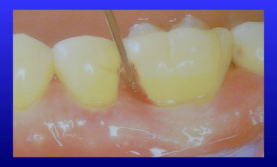

そこで、歯科医院ではポケット探針(下の写真)というハグキの溝を測る物差しで深さを測定します。

細い針の先のような道具で、先端から1ミリ単位のメモリが付いています。

ポケットの深さは1本の歯でも一定ではないので、歯を一周測ります。

通常、1本の歯について6つの場所の測定値を記録しておきます(6点法)。